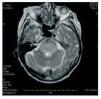

Dear Editor, The first description of myelinolysis dates from 1959. Since then, little progress has been made in determining its definitive cause, although we know the risk factors or the processes from which it arises. The most commonly reported form occurs in relation with rapid correction of hyponatraemia.1 It has also been described in alcoholism, liver transplant, and more rarely, following haemodialysis sessions not always related with changes in natraemia.2-4 In the latter, imbalance syndrome is much more common. However, there are circumstances that may cover both processes, especially during infancy.3 The clinical profile is characterised by an unexplained drop in level of consciousness, inability to look up, motor deficit in all four limbs, pseudobulbar syndrome, etc. In the proper clinical context, an MRI showing several indicative findings, especially at the protuberance,5,6 is an aid to diagnosis. The definitive diagnosis is by anatomical pathology. The course of the syndrome may be fatal even when it spares sensitivity and level of consciousness (locked-in syndrome), and treatment is purely conservative. Our 82-year old female patient, on haemodialysis throughout the past six months due to chronic renal failure (CRF) secondary to amyloidosis, was admitted for heart failure. She underwent an emergency dialysis session with 2500 ultrafiltration, and 24 hours later, a second ultrafiltration of 2000 given the scarce clinical and radiological signs of improvement. The patient, who initially presented a stable neurological state, began to show a strange clinical profile when finishing the second session of acute dialysis. It consisted of a low, fluctuating level of consciousness, absence of language ability, fixed gaze looking forward and loss of strength in the right arm and both legs. Specialised examination pointed to a dialysis imbalance process. Pre- and post-haemodialysis Na levels did not show significant abnormalities (136 to 132mEq/l), and neither were the changes in other parameters (urea, etc) outside of the normal range. We performed a cranial TC which detected an old thalamic lacunar infarct and cortico subcortical atrophy. The MRI showed significant hyperintensity throughout the protuberance and in the pontinemesencephalic union without diffusion restriction, which was therefore unrelated to ischaemia. Central pontine myelinolysis was then diagnosed. In the supratentorial area, she presented a significant hyperintensity in the periventricular white substance and an old lacunar infarct (Figure 1). Clinical progress was satisfactory after considering a regime of repeated short, daily haemodialysis sessions, and the condition resolved in six days. Obviously, considering the patient’s age and underlying condition, a sure diagnosis would be difficult to determine. However, we must underscore how unusual this acute neurological process was, following a year on dialysis, with no obvious changes in osmolarity, etc. However, it would seem that it could be related to aggressive dialysis sessions in a senile patient who may have been subjected to excessive ultrafiltration. The recovery time for the process, as well as the MR image, mean that we must consider a process of myelinosis.

Figure 1. Craneal magnetic resonance image.